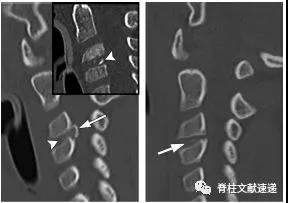

4.钙化椎间盘及骨赘导致脊液漏

- 1998年,Vishteh等人首次描述了腹侧硬膜外间隙钙化椎间盘骨赘导致脊髓脑脊液漏的原因。

- 钙化的椎间盘组织或骨赘骨刺导致硬脑膜缺损、由此产生的脑脊液漏和脑脊液低颅压表现。C5–T7常见。

图注:钙化椎间盘及骨赘导致脊液漏

图注:一位47岁女性因钙化椎间盘后方骨赘导致硬脑膜撕裂、脑脊液漏和颅内压过低。